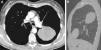

Presentamos el caso de una paciente joven asintomática, que presentó una masa torácica con un diagnóstico final de tumor neuroectodérmico primitivo (TNEP) intracisural. La paciente era una mujer de 27 años en la que se detectó accidentalmente una masa pulmonar en una radiografía de tórax. Todos los análisis de laboratorio dieron resultados normales. La tomografía computarizada (TC) mostró una masa elíptica, heterogénea, con captación de contraste, en el hemitórax izquierdo, de un diámetro de ∼12cm y bordes lisos. La masa estaba situada en el interior de la cisura oblicua de la pleura izquierda (fig. 1). La citología mediante aspiración por punción con aguja fina bajo guía de TC no fue concluyente. La resección quirúrgica evidenció una masa intracisural. La tinción de hematoxilina y eosina mostró un patrón de células redondas sólidamente compactadas con una sorprendente uniformidad. Inmunohistoquímicamente, las células tumorales eran intensamente positivas para MIC2 (CD99) y para vimentina. Otros marcadores, como citoqueratina (CK), cáncer de pulmón microcítico, cromogranina, CK7, CK19 y factor de transcripción tiroideo 1, fueron negativos. Los estudios de genética molecular con el empleo de hibridación de fluorescencia in situ mostraron una translocación positiva de los brazos largos de los cromosomas 11 y 22 [t(11;22)(q24;q12)]. Estos resultados eran compatibles con un TNEP. Los métodos estándares de estadificación, incluida la resonancia magnética (RM) cerebral, la RM de todo el cuerpo, la TC abdominal y la gammagrafía ósea, no detectaron metástasis a distancia. Tras una resección quirúrgica completa, la paciente fue tratada con quimioterapia. Posteriormente ha seguido un control ambulatorio y su estado se ha mantenido inalterado durante un período de seguimiento de 2 años.

La observación más frecuente en la TC en los TNEP es una masa con captación heterogénea de contraste. Ocasionalmente se observa un área central de baja densidad, sin captación de contraste, en el interior de la masa. El aspecto heterogéneo de las neoplasias grandes suele deberse a áreas focales de hemorragia o necrosis5.